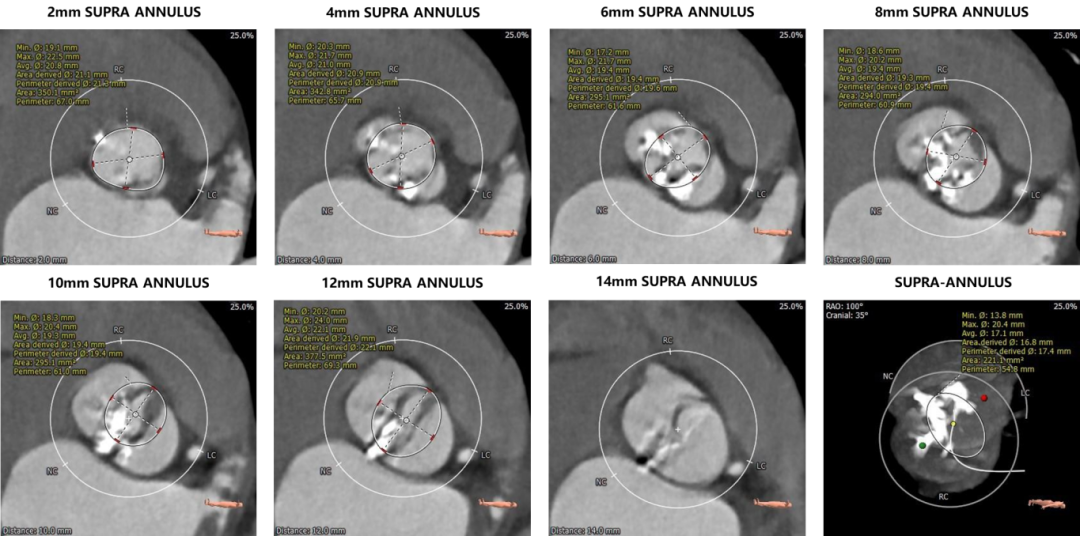

1.主动脉瓣瓣环周长69.0mm,平均周长径22.0mm。

2.Type0型二叶式主动脉瓣,左右冠不同窦,重度钙化,钙化分布欠均匀,右冠瓣尤甚,主要分布于瓣叶边缘及管壁附着缘,瓣叶增生肥厚。

3.左右冠开口高度较高,未见明显钙化,右冠瓣叶长度>右冠开口到右冠瓣叶附着缘距离。

4.瓦氏窦内径尚可,窦管交界内径可,升主动脉无扩张,LVOT内径大于瓣环,呈火山口状。

5.左室腔内径可,心室壁不厚。主动脉瓣环与水平面夹角54°,主动脉弓部夹角与弓距可。

主动脉根部评估:

根部概览

瓣环上解剖结构评估